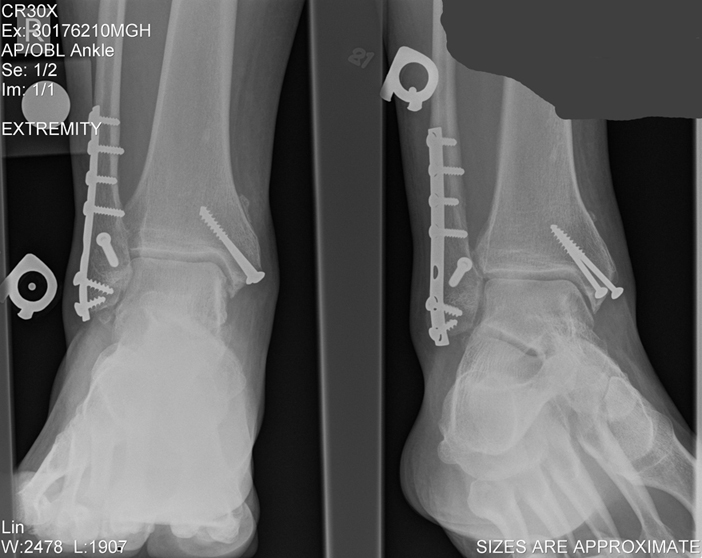

This is the break (both sides):

0010003.jpg

Here's the screws:

004.jpg

Notice where the big screws are, how one of them is sticking out a lot - that's what was hurting like a BITCH. Anyway, those 2 big screws are gone! Sweet, huh?